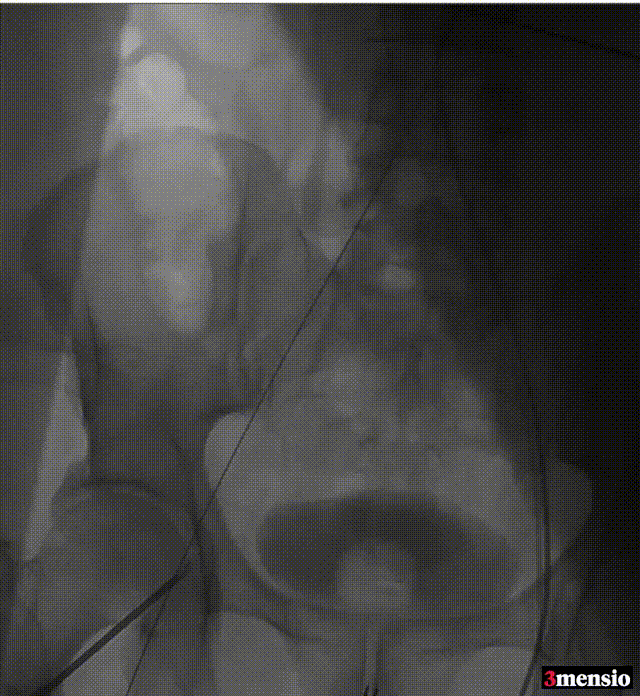

术前心脏超声结果显示,患者主动脉瓣开放明显受限,呈二叶式畸形(Type 1型),主动脉瓣前向血流Vmax 4.2m/s,峰值跨瓣压差71mmHg,平均跨瓣压差41mmHg,窦部内径31 mm,主动脉瓣环内径22mm;升主动脉瘤样扩张,内径50mm。

术前CT结果显示,主动脉瓣口面积495.3mm²,瓣环平均直径25.4mm,瓣环周长80.4 mm;LVOT面积432.1 mm²,LVOT平均直径24.1 mm;升主动脉平均直径51.5 mm;心夹角63°。